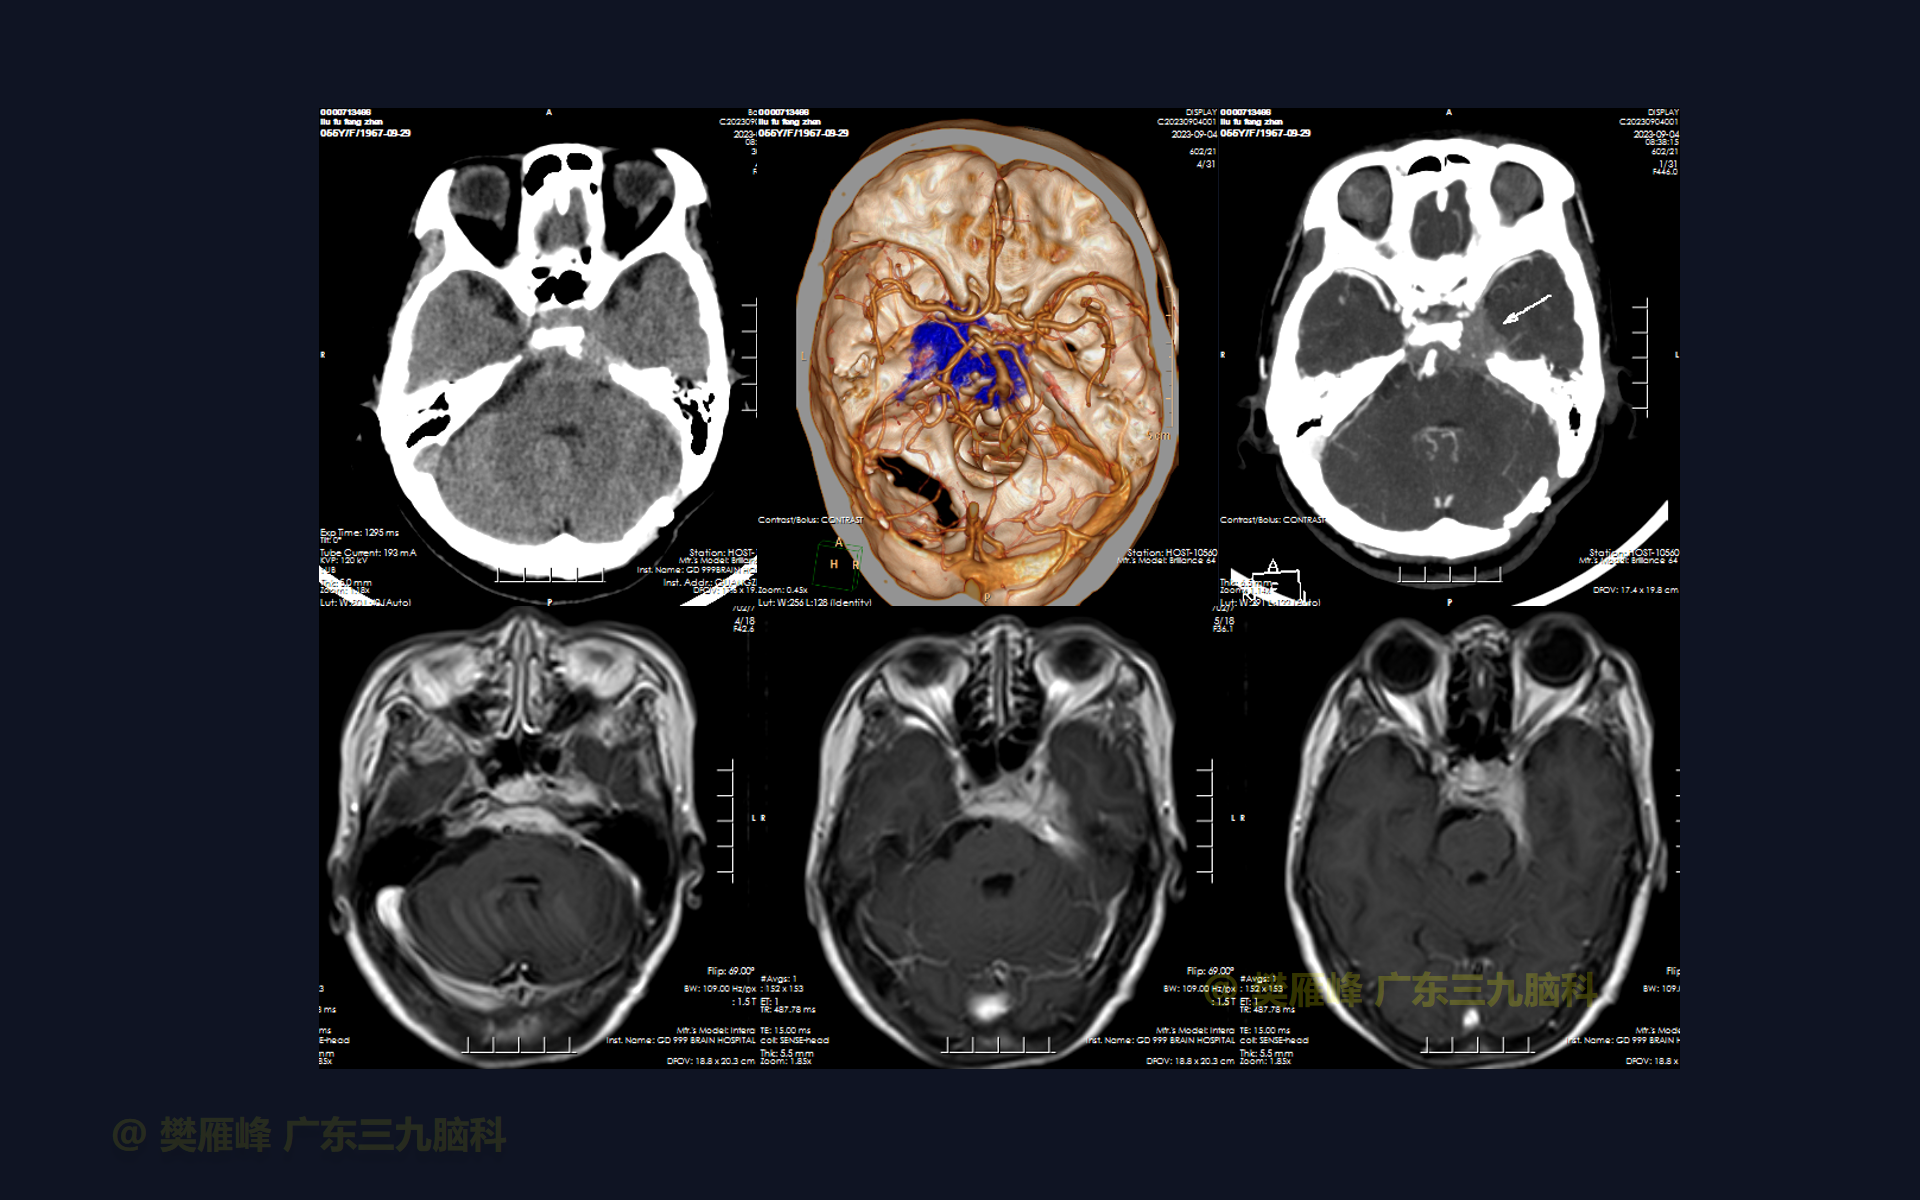

在这个二维手术视频中,展示了一种经扩大的中颅窝底入路硬膜外磨除Kawase三角切除蝶岩斜区复发脑膜瘤的方法。患者是一名55岁的女性,有6年的左耳听力下降行经乙状窦后入路岩斜脑膜瘤切除,术后左侧眼球运动障碍伴左侧面部歪斜、左侧听力下降;1月前复查发现蝶岩斜区脑膜瘤复发,神经影像学显示左侧鞍区、海绵窦、岩斜区团块状占位,累及蝶窦后部并侵进垂体窝,形态不规则,呈等T1等T2、FLAIR高信号为主,明显强化,邻近硬脑膜强化。他接受了经扩大的中颅窝底入路硬膜外磨除Kawase三角切除蝶岩斜区复发脑膜瘤,手术耐受较好,肿瘤大部切除。术后左侧眼睑下垂,左侧面瘫,左耳听力基本丧失等情况同前。神经影像学显示肿瘤大部切除。术后1月后行放疗。我们展示了安全的颅神经和肿瘤切除术的细微差别和技术要点,以及手术技术,以留下最少的残余粘附肿瘤。

在这段手术视频中,展示了一名55岁女性的病例,他因左侧眼球运动障碍伴左侧面部歪斜、左侧听力下降6年复查发现的左侧蝶岩斜区复发脑膜瘤。